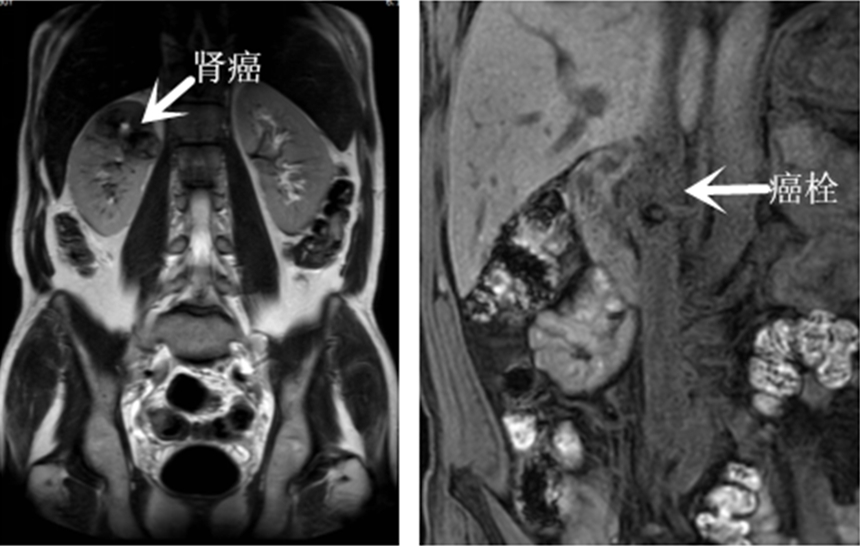

术前影像资料

患者体检发现肾脏占位性病变,就诊于当地医院行相关检查后诊断为右肾癌合并下腔静脉癌栓,同时合并糖尿病、颈动脉斑块,颈内静脉血栓及冠状动脉斑块等疾病。肾癌合并下腔静脉II级癌栓属临床少见病例,且患者患有多种基础疾病,手术风险极高。

鉴于患者的复杂病情经术前MDT讨论后实施了达芬奇机器人辅助下右肾癌根治+下腔静脉瘤栓切除术,术中血管阻断完全,取出癌栓长约5.2cm,病灶清除彻底,术中出血约50ml,手术顺利,患者康复出院。